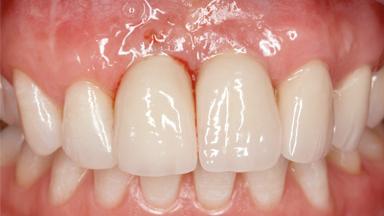

A 45-year-old woman was referred for management of an infection associated with two implant-supported crowns replacing the maxillary central incisors. Two tissue-level implants had been placed and restored with cemented single metal-ceramic crowns in those sites 4 years previously. The patient presented with a draining sinus (i.e. a pathological duct from an abscess cavity to a surface) 3 mm from the midfacial peri-implant mucosal margin of the maxillary right implant crown. She was in good general health, did not smoke, showed a good oral hygiene status, and had no history of periodontal disease. The implants were well positioned. While the patient was very satisfied with the appearance of her crowns, she had noted that the peri-implant soft tissue had receded since their insertion and was concerned about the possibility of further recession.